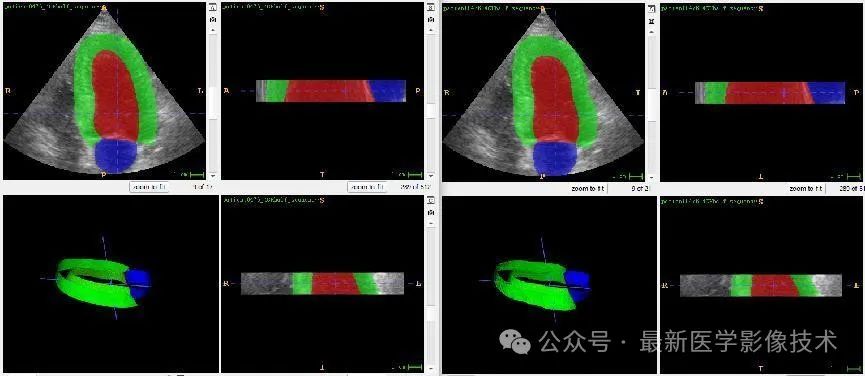

任务二、超声心动图3d结构分割

1、将图像缩放到固定大小512x512x48。图像预处理,再采用均值为0,方差为1的方式进行归一化处理,再将数据分成训练集和验证集,并对训练数据进行数据增强扩增5倍。

2、搭建VNet3d网络,使用AdamW优化器,学习率是0.001,batchsize是1,epoch是300,损失函数采用多类别的dice和交叉熵。

3、训练结果和验证结果

4、验证集部分分割结果

左边是金标准结果,右边是预测结果。